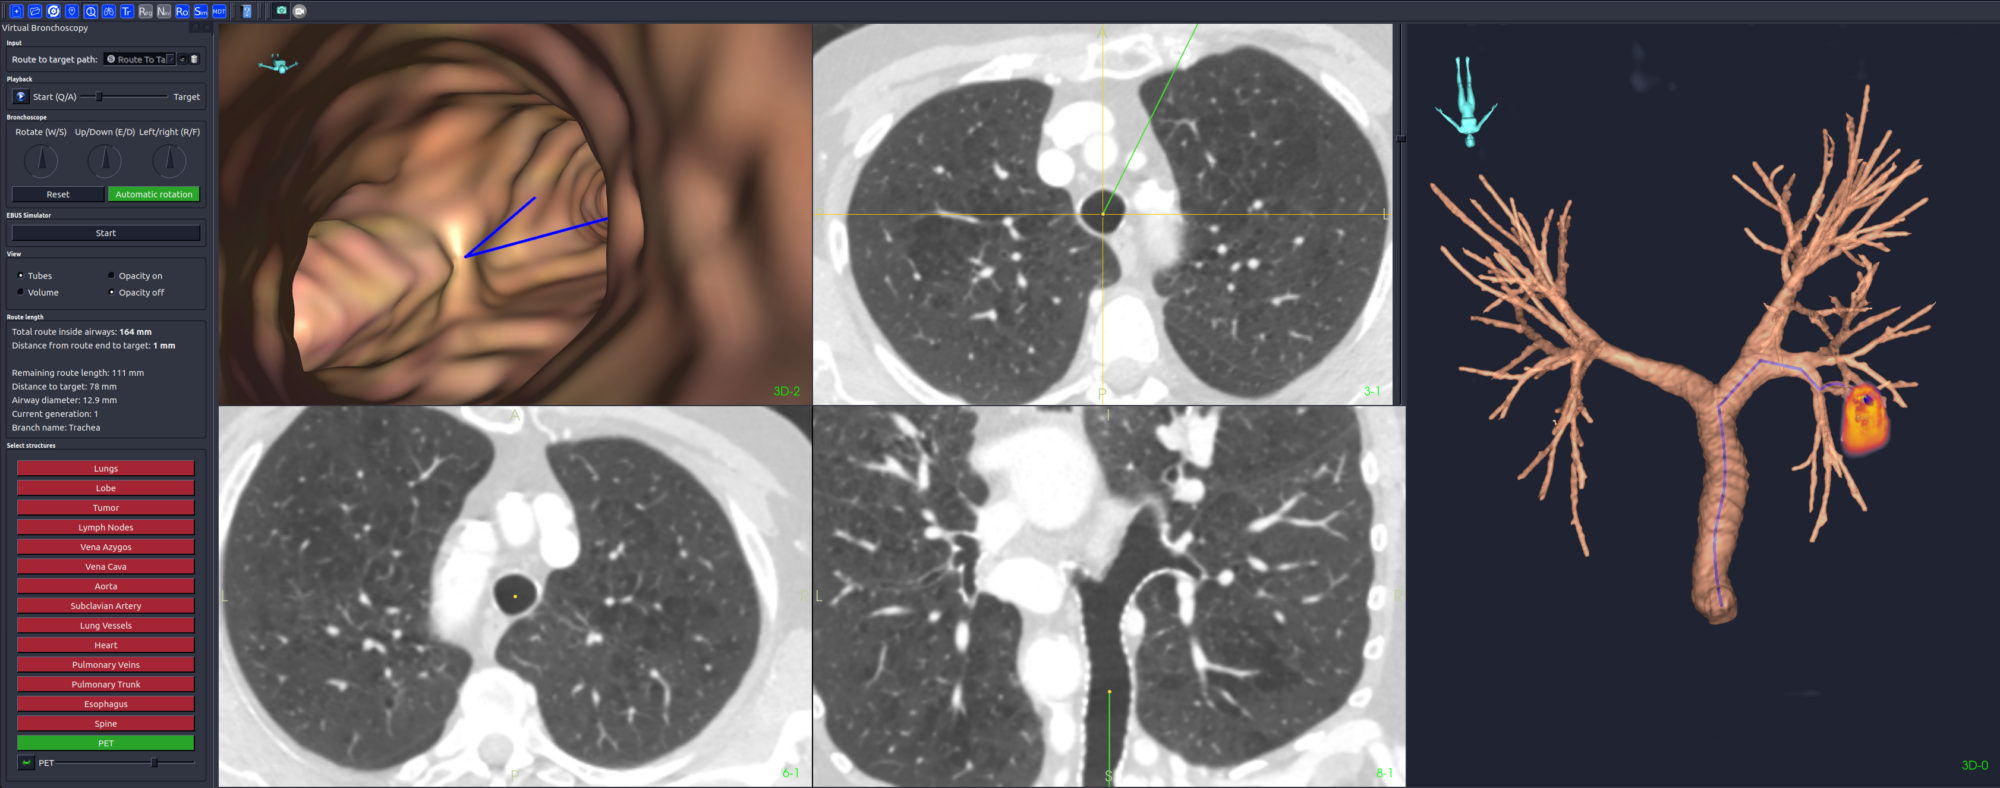

På en skjerm foran oss lyser et bilde av luftrørets indre. Glinsende, levende, og forstørret. Et bronkoskop, en tynn slange med et 2 millimeter lite kamera i tuppen, manøvreres sakte gjennom luftveiene, som en utforsker i kroppens egne labyrinter.

På en annen skjerm vises CT-bilder, anatomiske 3D-modeller og fargekodede markører. Dette er ikke bare en medisinsk undersøkelse, det er presisjonsnavigasjon i sanntid, og det skjer her og nå, på et behandlingsrom i Trondheim.

Dette er splitter ny teknologi i bruk: Sanntidsbilder fra bronkoskopet sammenstilles med den digitale modellen, og gir legene et veikart gjennom lungens forgreninger, som kan dele seg opptil 23 ganger før de ytterste lungeblærene nås.

Fraxinus bruker kunstig intelligens til å analysere CT-bildene av pasienten, og kan automatisk identifisere mellom ti og 15 anatomiske strukturer som luftveier, blodårer, lymfeknuter og eventuelle svulster. Tidligere måtte denne merkingen gjøres manuelt. Nå går det på sekunder.

– Du får rett og slett en tredimensjonal pasientmodell, hvor du kan planlegge hele veien frem til området man ønsker å ta en biopsi av, forklarer Erlend Fagertun Hofstad, teknolog og utvikler i prosjektet.

Systemet gir en «virtuell flyreise» gjennom lungene, og kan på sikt kombineres med navigasjonssystemer, robotikk, posisjonssporing og andre hjelpemidler. Allerede nå har slik teknologi vist seg å kunne doble treffsikkerheten ved bronkoskopi.

– Bare det å planlegge inngrepet med en 3D-modell gir markant forbedring, sier Hofstad.

– I noen studier har treffprosenten gått fra 30 til nesten 60 prosent, uten at man gjør annet enn å forberede seg bedre med 3D-modeller og en virtuell planlegging av veien frem til målet i lungene.